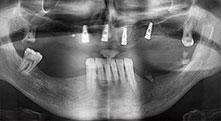

Проф. д-р Емануел Брату, лицево-челюстен хирург, орален хирург и протезист, е ръководител на имплантологичните департаменти в два румънски университета. Той управлява известна частна болница в Тимишоара и е международно признат изследовател. В това интервю Брату обяснява защо той смята, че апаратът за пиезо хирургия Piezomed на W&H и двата патентовани триони са от съществено значение за костната хирургия.

Брату: Ние използваме инструментите за събиране на костни блокове и разделяне на алвеоларни гребени. Ние също използваме Piezomed B6/B7 за остеотомия на наранени зъби и отстраняване на неуспешни импланти. Всички индикации, които изискват дълбоки, чисти разрези.

Брату: Ние предпочитаме да използваме техниката "сандвич" за аугментация в страничната долна челюст. Покритие на костта се подготвя с пиезо трион и кресталният фрагмент се фиксира с микровинтове. Поставяме смес от автогенна костна присадка и ксеногенен костозаместител между тях. Това работи много надеждно. Трябва винаги да осигурявате достатъчно оразмерени вертикални срезове при шиниране на алвеоларния гребен в долната челюст. В противен случай, костта лесно може да бъде счупена.